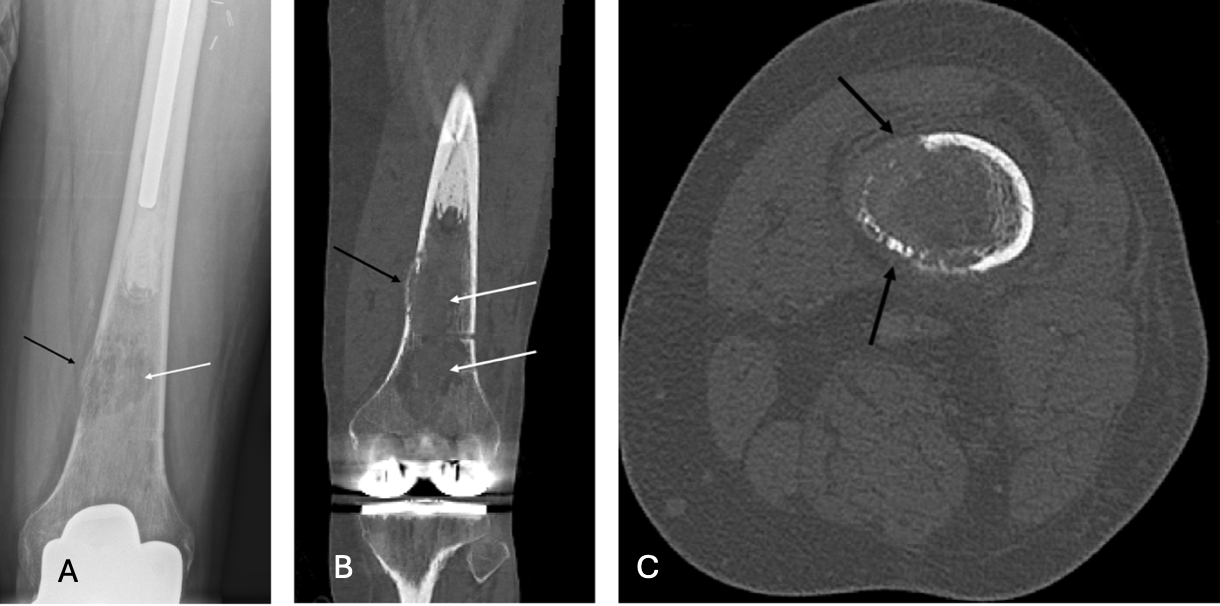

One year later, follow-up radiographs revealed an aggressive, permeative, marrow-replacing lesion in the distal femoral metadiaphysis, confirmed by CT to have cortical destruction and aggressive growth (Figure 5)4,5, consistent with low-grade sarcoma on biopsy.

Figure 5A-C. Plain radiograph (a), coronal CT (b), and axial CT (c) of left distal femur. New lucent, aggressive marrow-replacing lesion (white arrow) of the distal femoral diametaphysis with cortical thinning and permeation (black arrow), corresponding with biopsy-proven low-grade osteosarcoma.